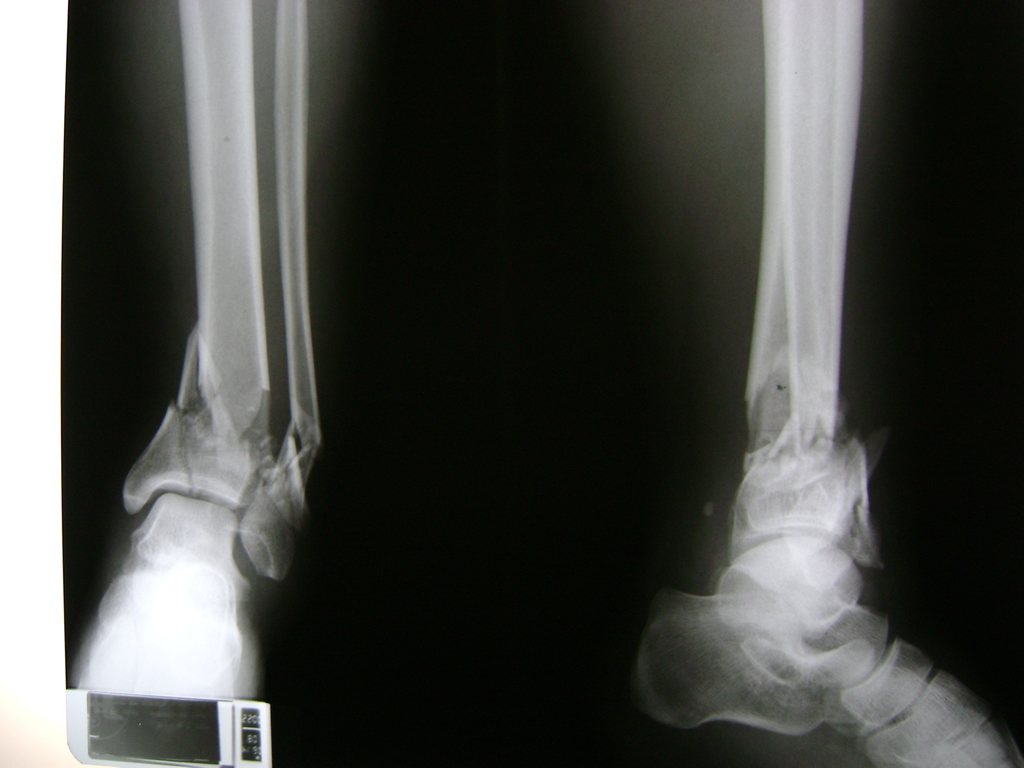

Una fractura de tobillo es la rotura de uno o más de los huesos del tobillo. Estas fracturas pueden ser:

- Parciales (el hueso está sólo parcialmente fisurado, no del todo).

- Completas (el hueso está perforado y está en 2 partes).

Algunas fracturas de tobillo pueden requerir cirugía si:

- Los extremos de los huesos están desalineados entre sí (desplazados).

- La fractura se extiende hasta la articulación del tobillo (fractura intra-articular).

- Los tendones o ligamentos (tejidos que sujetan los músculos y los huesos entre sí) están rotos.

Cuando se necesita cirugía, es probable que esta implique el uso de clavijas de metal, tornillos o placas para sostener los huesos en su lugar mientras la fractura se consolida. Los elementos de soporte pueden ser temporales o permanentes.